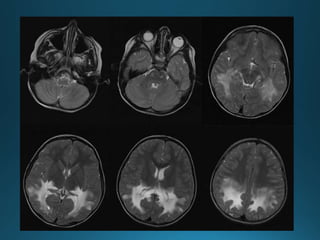

Cytomegalovirus (CMV) encephalitis is a CNS infection that

almost always develops in the context of profound

immunosuppression

In CMV encephalitis, there is usually only non specific increasedT2/FLAIR

signal in the white matter. If ventriculitis is also present then enhancement of

the ependymal surface and hydrocephalus may also be seen.

highT2 white matter change most prominent in a periventricular distribution

no enhancement (unless ventriculitis present, in which case 30% or so will

enhance)

no mass effect (often seen with concurrent atrophy)